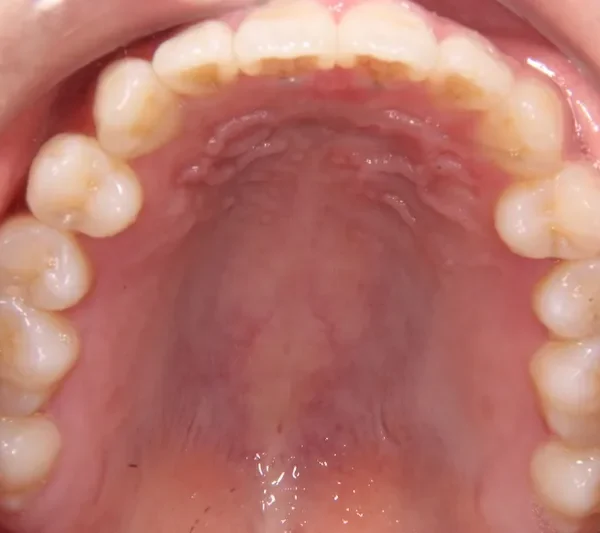

初診時年齢 19~29歳 (女性) 主訴 前歯で物が噛みちぎれない

診断名 開咬・上顎前突 装置名

特徴 固い食べ物が嫌い

上の歯と下の歯で舌をはさむ癖がある

前歯で物が噛みちぎれないを主訴に来院された患者様です。

非抜歯で、オリジナルリンガルアーチと歯科矯正用アンカースクリューを用いて治療しました。

治療回数15回、1年の治療期間で矯正治療を終了しました。

主訴が改善され、ご満足頂きました。